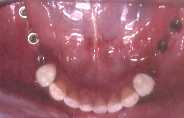

Komence oni pensis nur anstataŭi la malsupran dentaron, kie estas plej malfacile fari depreneblan protezon. Tiucele oni bezonis 6 implantojn en la antaŭa parto de la mandiblo, kaj sur tiuj oni povos konstrui 10 aŭ eĉ 12 dentojn, solvante unu el la plej grandaj problemoj de la sendentaj homoj.

La kazo de alia sinjorino: Ŝi perdis la dentojn pro gingivaj malsanoj - ŝi ne scias bone zorgi pri siaj dentoj kaj gingivoj - kaj finfine ili estis preskaŭ falantaj. Oni devis forpreni ili, kaj anstataŭi ilin per metalaj radikoj (kompreneble, titanaj radikoj), post 6 monatoj oni malfermis ilin, oni faris provizorajn dentojn ĝis la ripariĝo de la gingivo, kaj fine oni konstruis porcelanajn dentojn.

De la perdo de la naturaj dentoj ĝis la fino de la kuracado, ŝi uzis , kompreneble, tutan depreneblan superan protezon, kaj ŝi ne estis feliĉa, ĉar ŝi ne povis bone maĉi. Kaj tio okazas al ĉiuj homoj, kiuj uzas artefaritan dentaron. Ekzemple: Ili ne povas mordi malmolajn manĝaĵojn ĉe la antaŭaj dentoj, ĉar tie estas la plej tikla loko de la superaj (kaj ankaŭ de la malsuperaj) dentaroj. Ili simple foriras de la gingiva bazo, kie ili kuŝas, se la homoj manĝas ekzemple pomon. Kaj post la kuracado ŝi estis tre feliĉa, ĉar ŝi denove povis mordi pomon.

Dum 25 jaroj ŝi restis sen la antaŭaj dentoj, kaj pro tio la superaj postaj dentoj malsupreniris. Do mi devis fari kirurgion por suprenirigi la dentojn. Post la ostointegriĝo de siaj implantoj, oni malfermis la gingivon, faris provizorajn plantajn dentojn, kaj fine ŝi ricevis porcelanajn kronojn. Kaj nun ŝi povas perfekte ne nur manĝi sed amkaŭ ridi, prelegi, kaj eĉ preĝi sen la timo, ke la dentoj povu fali.